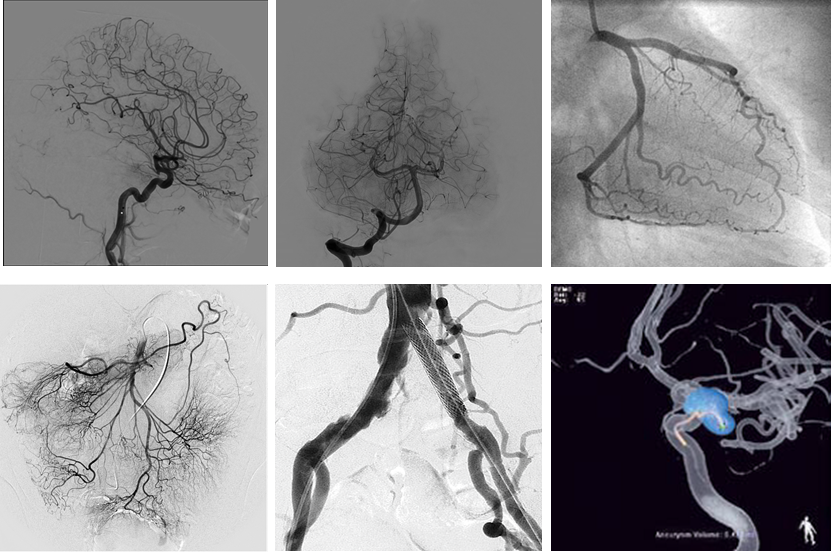

2.外周血管介入手术治疗:腹主动脉血管病症,肝脏肿瘤治疗,肝脏,肺部肿瘤活检,椎体成形术,泌尿系统血管病变等微创介入手术。

左下肺动脉造影 右下肺动脉造影 图左:腹主动脉瘤造影 图右:腹主动脉瘤支架植入造影